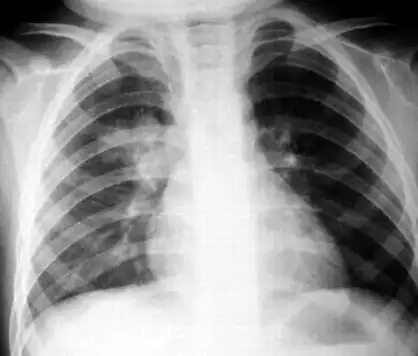

儿童肺炎时胸片怎么看呢

胸片可见两肺弥漫炎性渗出影,因此诊断为小儿支气管肺炎